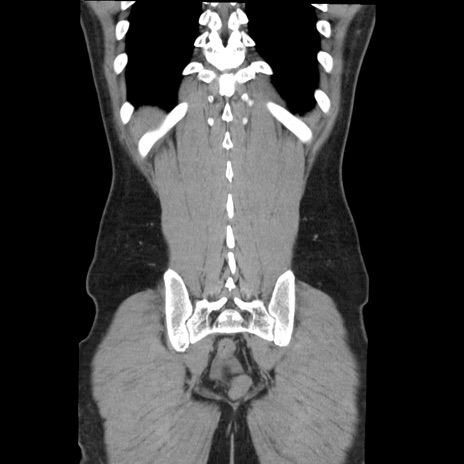

症例36(冠状断像)

【症例】20歳代 男性

【主訴】心窩部痛

【現病歴】今朝より上腹部痛あり。一旦軽快していたが再度出現したため救急要請。昨日夕に白身の魚を含む刺身を食べた。

【身体所見】BP 136/89mmHg、HR 74/min、BT 37.0℃、腹部:膨満、軟、心窩部に圧痛あり。反跳痛なし、筋性防御なし、腸雑音やや亢進あり。

【データ】WBC 17700、CRP 0.48